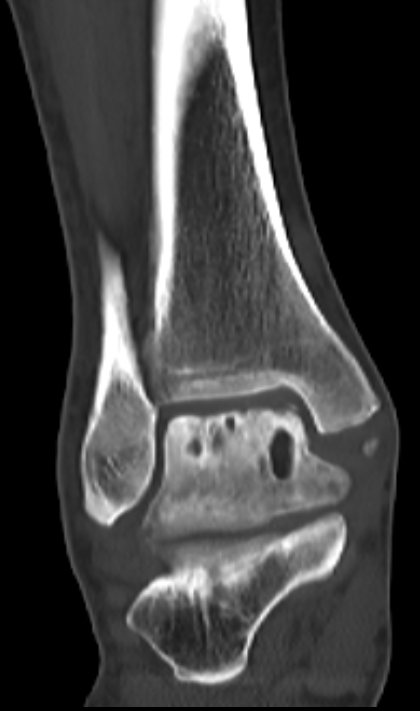

第二位是54岁的大哥,“脚脖子”痛了3年,检查发现只有部分距骨出了问题。

术前磁共振

术前CT

针对这种局部病变,团队用了3D打印部分距骨置换术。

这种手术不用大动,只换病变的那部分距骨,尽量保住健康的关节组织,创伤小,术后恢复起来也能快一点。